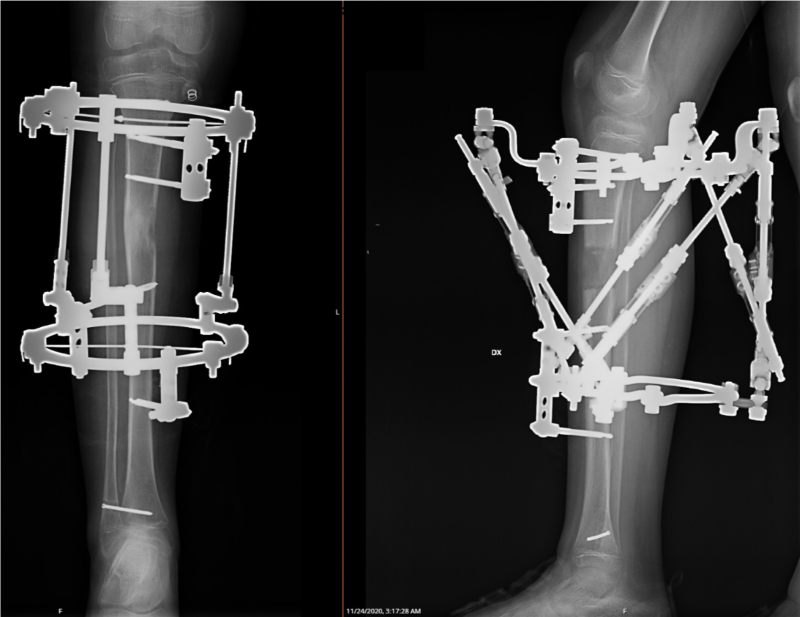

Ekstremitāšu rekosntruktīvā ortopēdija nozīmē operāciju un tai sekojošu operētās zonas korekciju ar ārējās fiksācijas aparāta, t.s. ortopēdiskā heksapoda palīdzību. Operācija noris, izmantojot spinālo vai vispārējo anestēziju, un ilgst līdz 2 stundām. Pacientam klīnikā jāuzturas vienu diennakti.

Operācijas laikā tiek veikta osteotomija (kontrolēts lūzums) un uzstādīts ortopēdiskais heksapods – ārējās fiksācijas aparāts, ar kura palīdzību iespējams veikt gandrīz jebkuras deformācijas precīzu korekciju.

Ekstremitāšu rekonstruktīvā ortopēdija notiek ķirurģiski ar ārējās fiksācijas - t.s. ortopēdiskā heksapoda palīdzību.